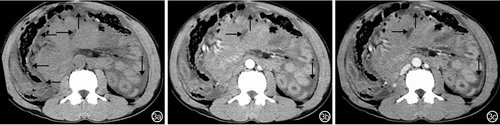

急性胰腺炎患者CT检查主要表现为局限性、节段性或弥漫性肠壁环形向心性增厚呈低密度“双环”、“三环”或“靶征”(图6);肠外主要表现为腹腔积液、胰腺增大密度减低、胰周脂肪肿胀、腹膜炎。(点击图片可查看原图)

图6 急性胰腺炎患者CT检查特征 6a:平扫示右肾前筋膜增厚(→)、十二指肠壁明显增厚(↓);6b:动脉期肠壁呈“三环”或“靶征”(↓);6c:静脉期肠壁强化程度较动脉期均匀(↓)

肠梗阻患者CT检查主要表现为回结肠肠壁弥漫性环形增厚,呈水样密度影,不强化或轻度强化;肠外主要表现为肠系膜肿胀、出血,腹腔积液(图7)。

肠系膜上动脉病变患者CT检查主要表现为肠壁广泛均匀中度增厚;肠外主要表现为腹膜炎和腹腔积液(图7)。

肠扭转患者CT检查主要表现为小肠局限性中重度增厚;肠外主要表现为腹膜炎、腹腔积液(图7)。(点击图片可查看原图)

图7 肠扭转并肠系膜血管病变患者CT检查特征 7a:平扫肠梗阻、肠系膜根部扭转(↓),轻度均匀强化,空肠扩张、腹腔积液(→);7b:动脉期回肠壁中度弥漫性均匀增厚(↑),明显均匀强化;7c:静脉期肠系膜上动脉回肠支夹层(↓)、空肠扩张(→)、腹腔积液